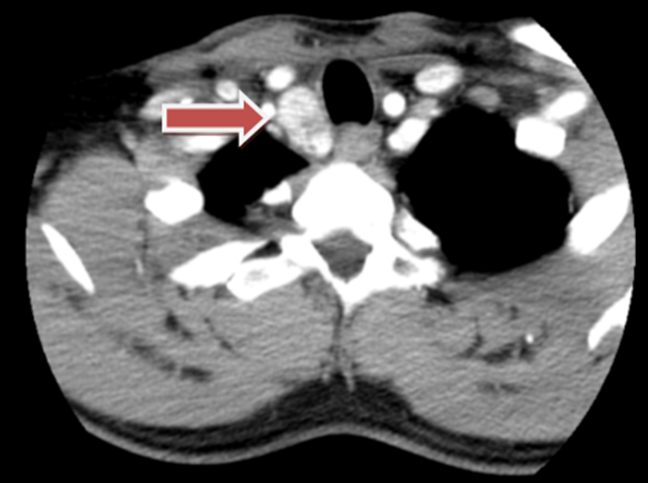

Hình ảnh chụp CT cổ ngực ngày 10/07/2023 phát hiện khối vị trí tuyến giáp ở bên phải nghi ngờ ung thư tuyến giáp tái phát